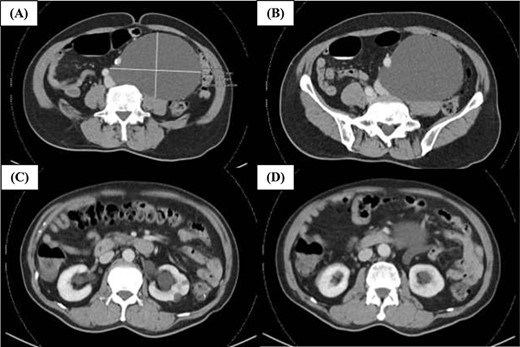

Computed tomography (CT) of the abdomen and pelvis indicated a well-circumscribed hypodense structure in the left side of the retroperitoneum adjacent to the aorta, the left common iliac artery and left common iliac vein measuring 13 cm × 9.7 cm × 15.8 cm where retroperitoneal lymphangioma was a consideration (Fig. 1). There was no significant thickened septation or mural nodularity. The low-density well-circumscribed left retroperitoneal lesion appeared to be cystic in nature displacing the left common iliac artery anteriorly. The left ureter was also displaced anteriorly resulting in mild left hydroureteronephrosis. The case was presented and discussed at a multidisciplinary tumour board where imaging was reviewed and there were no aggressive features seen. Differentials included a retroperitoneal cystic lymphangioma, mesenteric cyst or peritoneal inclusion cyst. Surgical resection was recommended. The patient elected to proceed with resection of the retroperitoneal tumour.

Representative CT images of the retroperitoneal lymphangioma. (A) Well-circumscribed hypodense structure in the left side of the retroperitoneum adjacent to the aorta, left common iliac artery and left common iliac vein measuring ~13 cm × 9.7 cm × 15.8 cm. There is no significant thickened septation or mural nodularity. (B) The left common iliac artery is displaced anteriorly. (C and D) There is mild mass effect resulting in mild dilatation of the left renal pelvicaliceal system and upper ureter. Both kidneys show symmetrical enhancement and renal cortex is of satisfactory thickness.